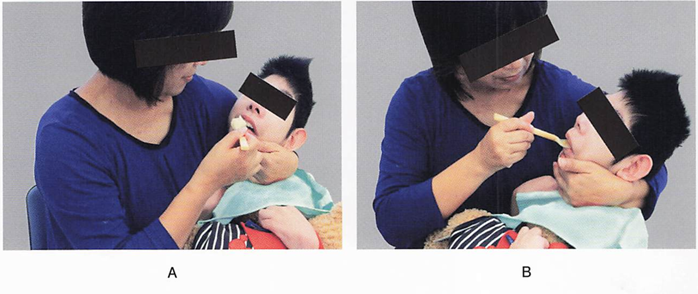

17歳の女子。脳性麻痒の診断を受けており、 家族から「最近食事の時にむせるのが気になる。」と相談を受けた。家族の食事介助の様子を別に示す。 家族への指導として適切なのはどれか。2つ選べ。

a. 頭をやや前屈きせましょう。

b. 一口量を少なくしましょう。

c. 横向きに寝かせて食べさせましょう。

d. ボウル部の深いスプーンを使いましょう。

解答を見る

a.b